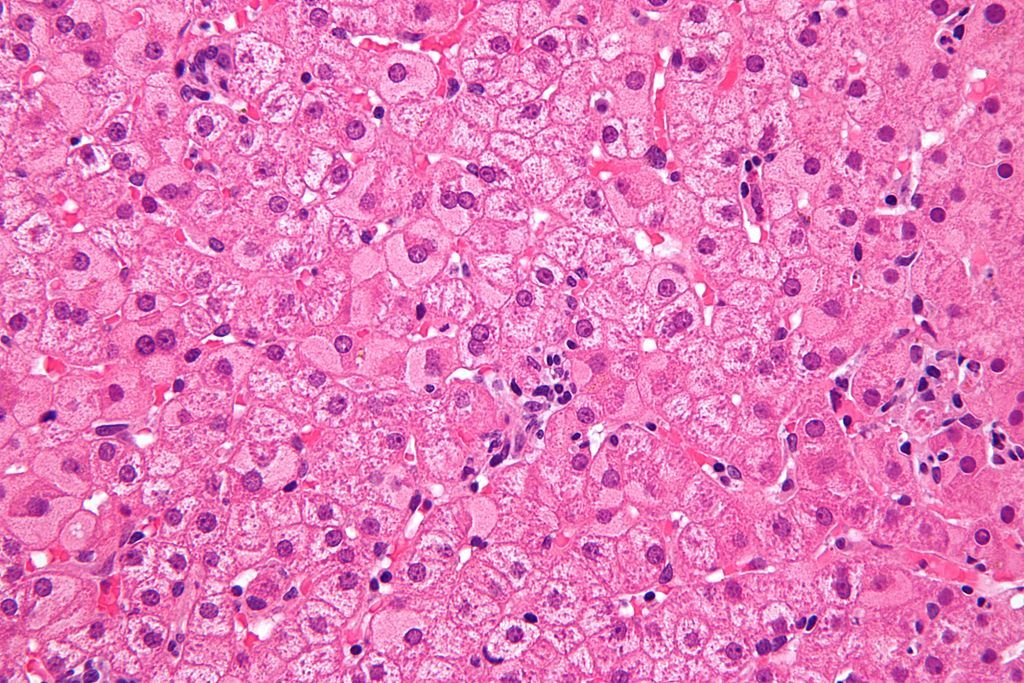

Milchglashepatozyt

Hepatozyt mit aufgetriebenem, transparentem Zytoplasma. Entsteht durch Hyperplasie des endoplasmatischen Retikulums, das wiederum durch eine gesteigerte Produktion des viralen Hüllmaterials (HBs-Antigen) bedingt ist HEPATITIS

Mottenfraßnekrose

Periportale Leberzellnekrose mit lymphozytärer Infiltration . Sie spricht für eine chronisch aktive Hepatitisform und ist ein prognostisch ungünstiges Zeichen